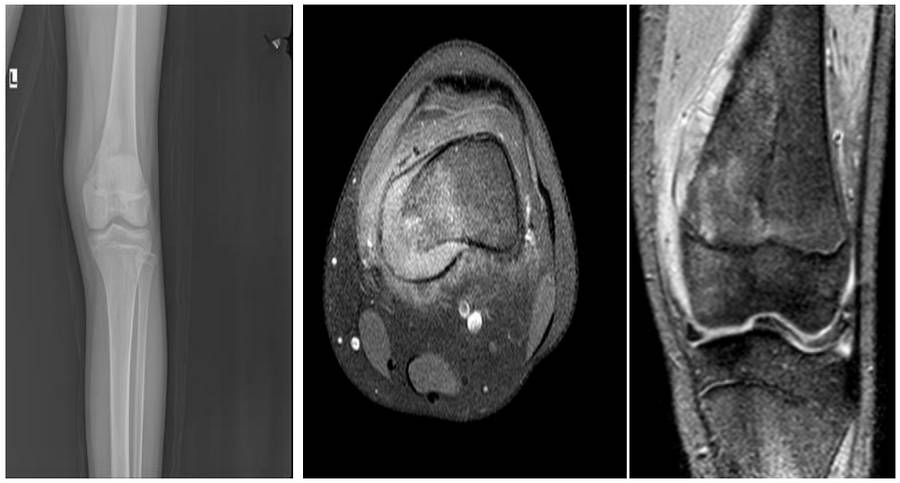

VAKA 15: Diz (Distal Femur) Yerleşimli Osteosarkom

Distal femur medial yerleşimli osteosarkom nedeniyle kemoterapiyi takiben hemikortikal rezeksiyon sonrası sıvı azot ile geri kazanım ve vaskülerize fibula ile kombinasyon uygulanan genç kadın hastamız

Ameliyat Öncesi: Röntgende distal femur medialde düzensizlik, MR’da aynı lokalizasyonda harabiyet ve yumuşak dokuya uzanan tümör dokusu görülmekte